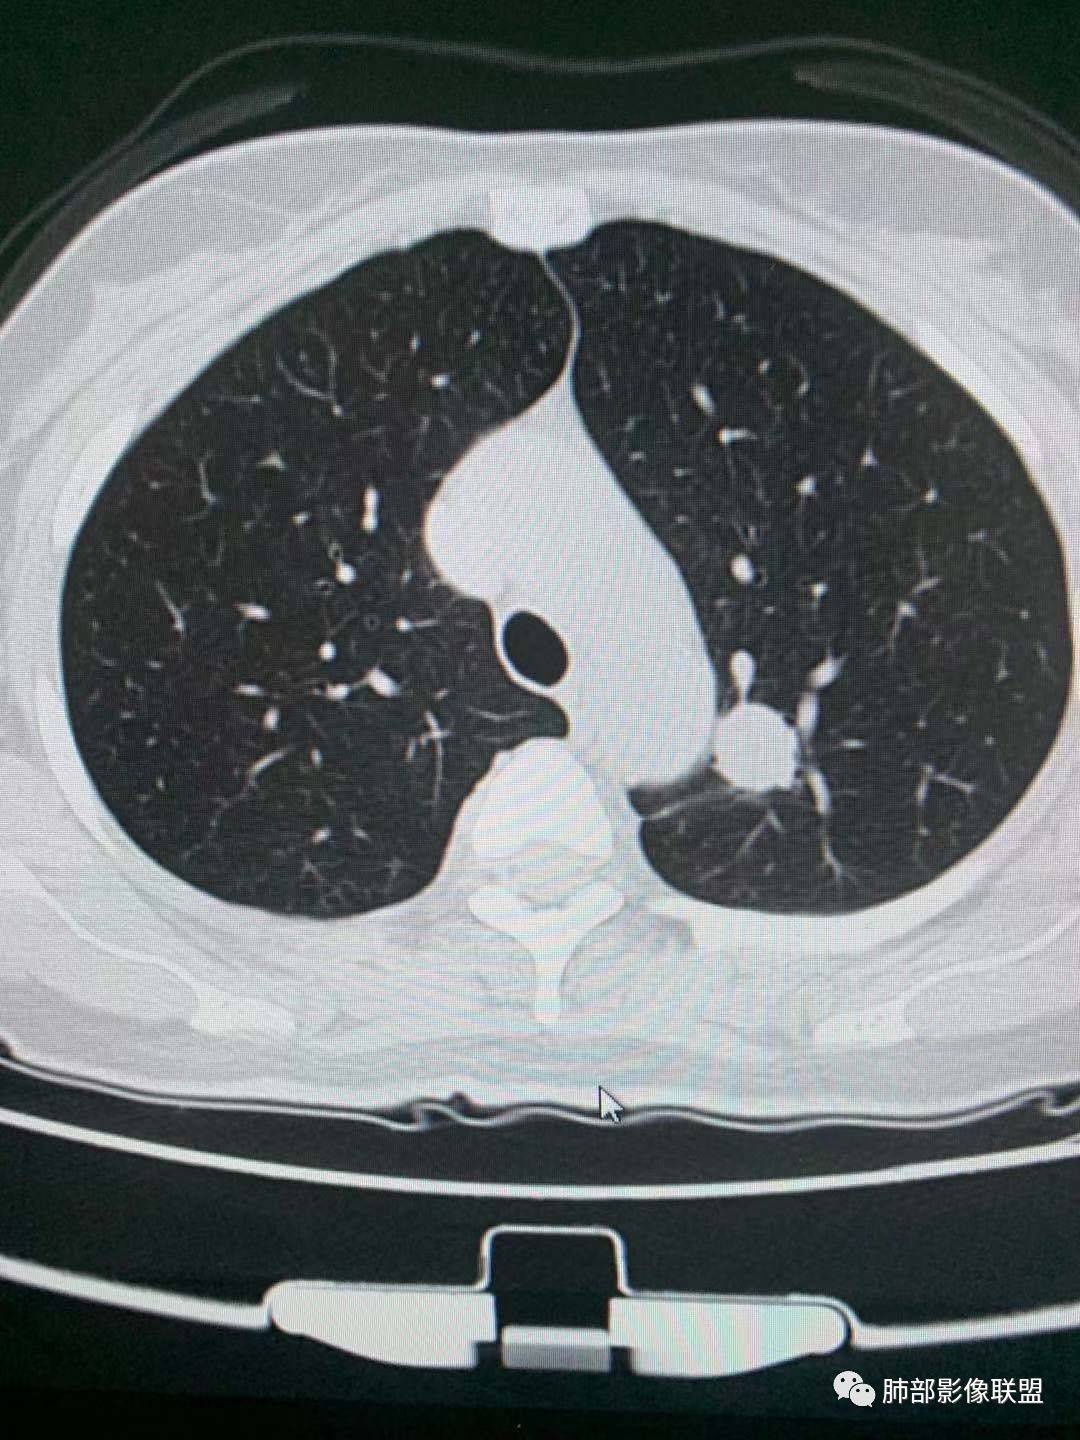

肺磨玻璃结节观察步骤

A

1.密度(纯磨玻璃pGGO、混合磨玻璃mGGO)

2.边界(是否清楚,清楚GGO偏向肿瘤,模糊GGO偏向炎性病变)

3.看边缘及内部征象(有无分叶、毛刺、血管集束征、空泡征、支气管征、胸膜凹陷征)

4.如果倾向肿瘤性病变,可以测CT值及大小,尤其纯磨玻璃结节,结合结节的高危征象,进一步判断早期肺腺癌的亚型分型。

5.如果倾向炎性病变,建议抗炎治疗后2周后随访复查。

三.右肺上叶胸膜下结节及左肺上叶血管旁结节,尽管都是磨玻璃密度,但都比较小且边缘特征不明显,恶性征象未显露,处置并无特殊,定期复查!